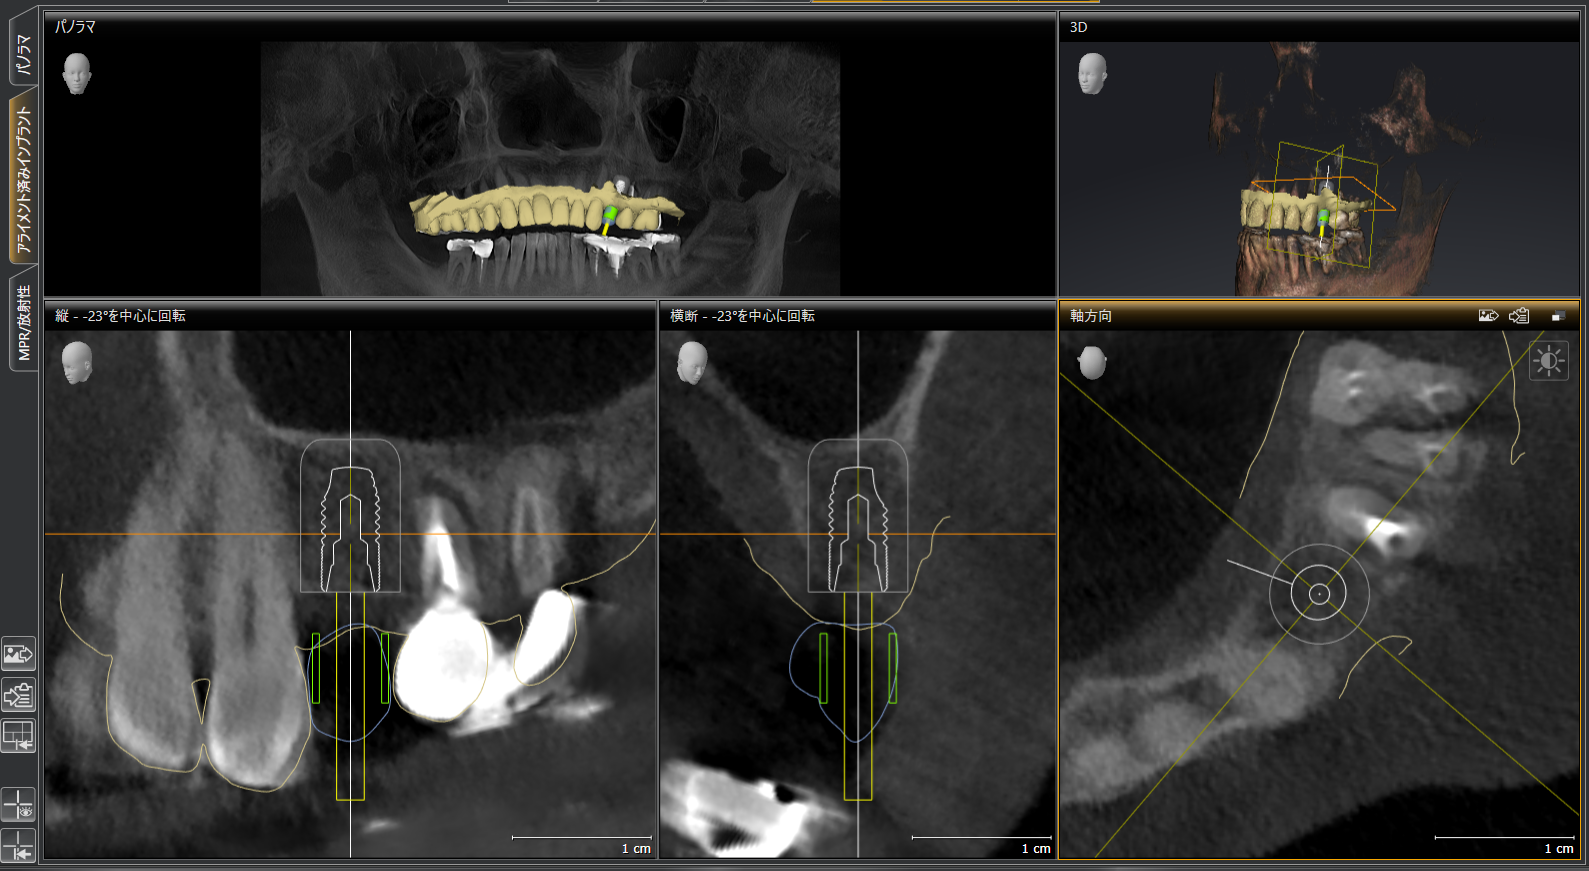

シュミレーション画像